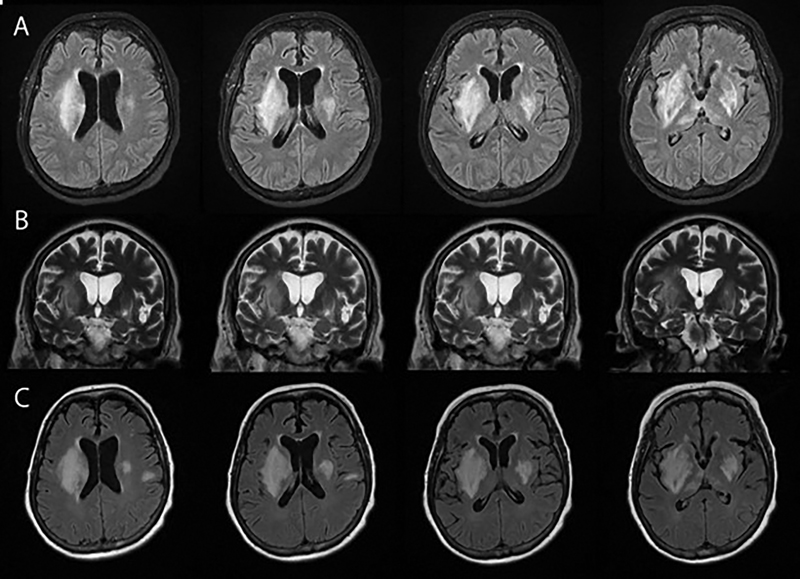

An ear biopsy was performed by dermatology on HD 15 after two previous refusals by the patient. Results showed spongiotic dermatitis with lymphocytes and plasma cells suggestive of relapsing polychondritis (HD 21). Paraspinal muscle biopsy also showed a focus of plasma cells in the connective tissue surrounding a vessel and suggested vasculitis. High-dose methylprednisolone (1g q24) were immediately started and the patient showed initial clinical improvement. However, the patient began declining on HD 23 with a worsening neurological examination, including new onset left upper extremity weakness. Paraspinal biopsy was suggestive of vasculitis. A repeat MRI showed new lesions in the right pons and midbrain (Figure 2). The patient continued to decline and became unresponsive to verbal stimuli. The patient also developed a fever of 103.2° F on HD 25. Given the patient’s declining condition and lack of additional treatment options, the patient’s family decided on comfort care, and the patient died on HD 26.

Figure 2

Figure 2. (A) and (B) Final MRI sequence (HD 23) and (C) Initial MRI (HD 2) of head.